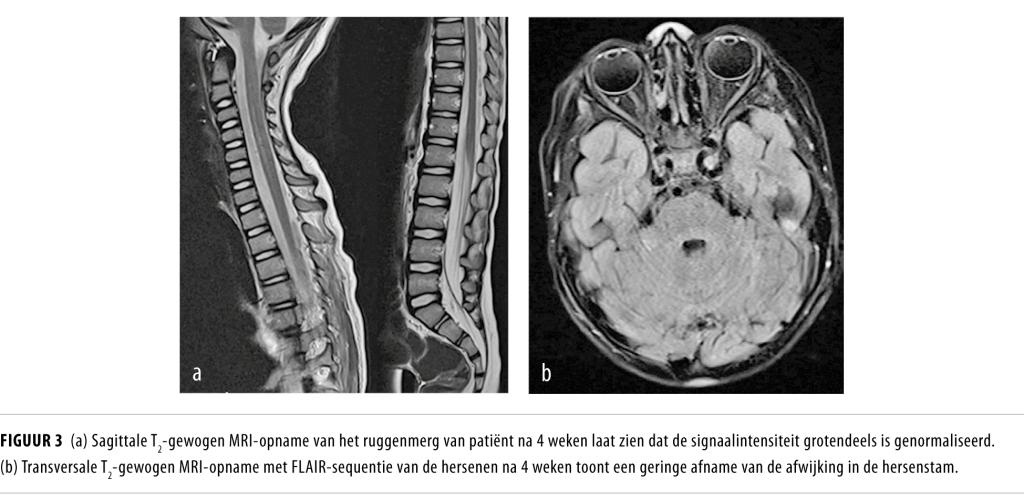

Bij progressieve spierzwakte na een luchtweginfectie moet gedacht worden aan enterovirusgerelateerde acute slappe verlamming. Deze ziekte onderscheidt zich van het Guillain-Barré-syndroom door snellere progressie, grotere betrokkenheid van de armen en asymmetrische uitval. De diagnose kan worden bevestigd met typische bevindingen bij emg en MRI van het ruggenmerg en de hersenstam, in combinatie met het aantonen van EV-D68 in luchtwegmateriaal.